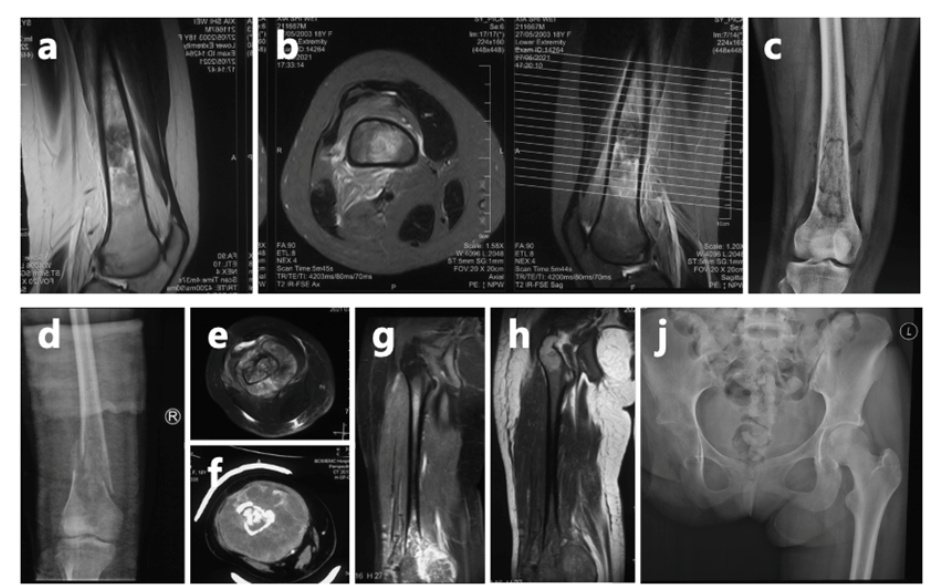

市一骨肿瘤科介绍,对于夏夏来说,此前的截肢是一个相对可靠的选择。由于肿瘤已推挤下肢的血管和神经,并累及髋关节,截肢手术能够降低肿瘤复发的几率。然而,截肢会导致术后肢体功能的永久性丧失,对患者心理和生活质量可能造成一定影响。尽管困难重重,她始终以微笑和坚韧面对一切。

夏夏前期接受了术前化疗、截肢手术及术后化疗,使用的是一线化疗方案。然而,结疗不到一年,肺部出现转移病灶,这种情况是恶性肿瘤的普遍特性,骨肉瘤患者中并不少见,尤其是结疗后2年内,是转移和复发的高发期。

为帮助她巩固疗效并延长无病生存期,2024年2月,夏夏经过手术切除后未再进行化疗。术后5个月,左肺再次发现新发转移病灶。2024年11月,夏夏接受胸腔镜下右肺下叶切除术。2025年1月复查:右肺术后改变好转。